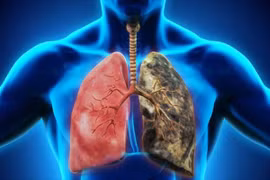

Tỷ lệ người chưa từng hút thuốc mắc ung thư phổi gia tăng, trong đó ô nhiễm không khí được xem là "yếu tố quan trọng" gây bệnh, theo Cơ quan Nghiên cứu ung thư quốc tế (IARC) thuộc Tổ chức Y tế thế giới (WHO).

Khoảng 80% bệnh nhân ung thư phổi được chẩn đoán khi bệnh đã ở giai đoạn muộn... Vì vậy, dự phòng, sàng lọc nhằm phát hiện ung thư phổi ở giai đoạn sớm là hết sức quan trọng.